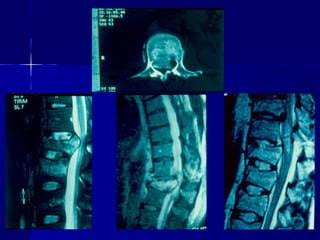

CCTT -- ssccaann

–PPoosstteerriioorr aarrcchh

wweellll ddeeffiinneedd

–RReettrrooppuullsseedd

ffrraaggnneennttss

ccoorrdd -- nneerrvveess

ccoommpprroommiisseedd

–AAddjjaacceenntt lleevveell

iinnjjuurryy –– 1100%%

MMRRII

–UUsseeffuull ttoo eevvaalluuaattee

ddiissccrreeppaannccyy

bbeettwweeeenn cclliinniiccaall

eevvaalluuaattiioonn aanndd xx--

rraayy // CCTT ffiinnddiinnggss

–DDiisscc hheerrnniiaattiioonn

–LLiiggaammeennttoouuss

iinnjjuurryy